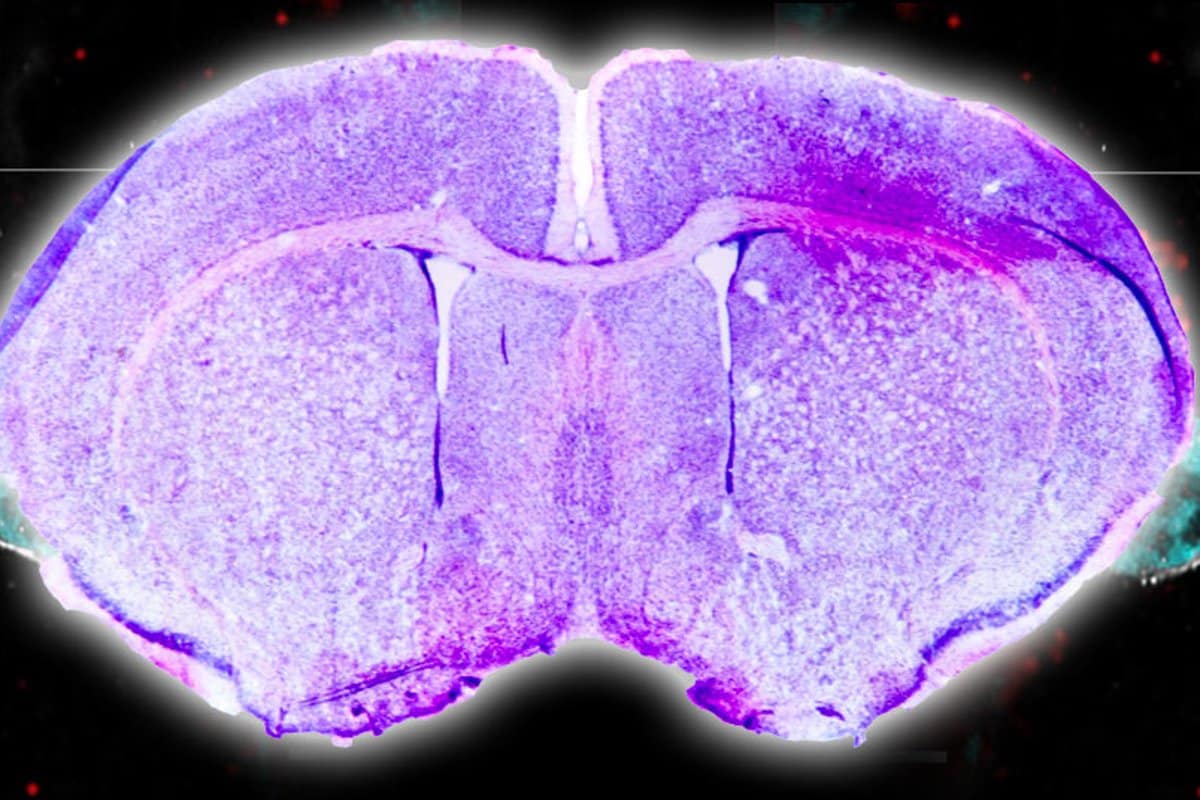

Immune system cells in female rat brains consume and digest neurons, sculpting a specific brain region during development and potentially impacting behavior. This insight into the interplay between biological sex, the immune system, and brain development may pave the way for understanding why certain brain disorders are more prevalent in one sex and could inform future treatments or prevention strategies.